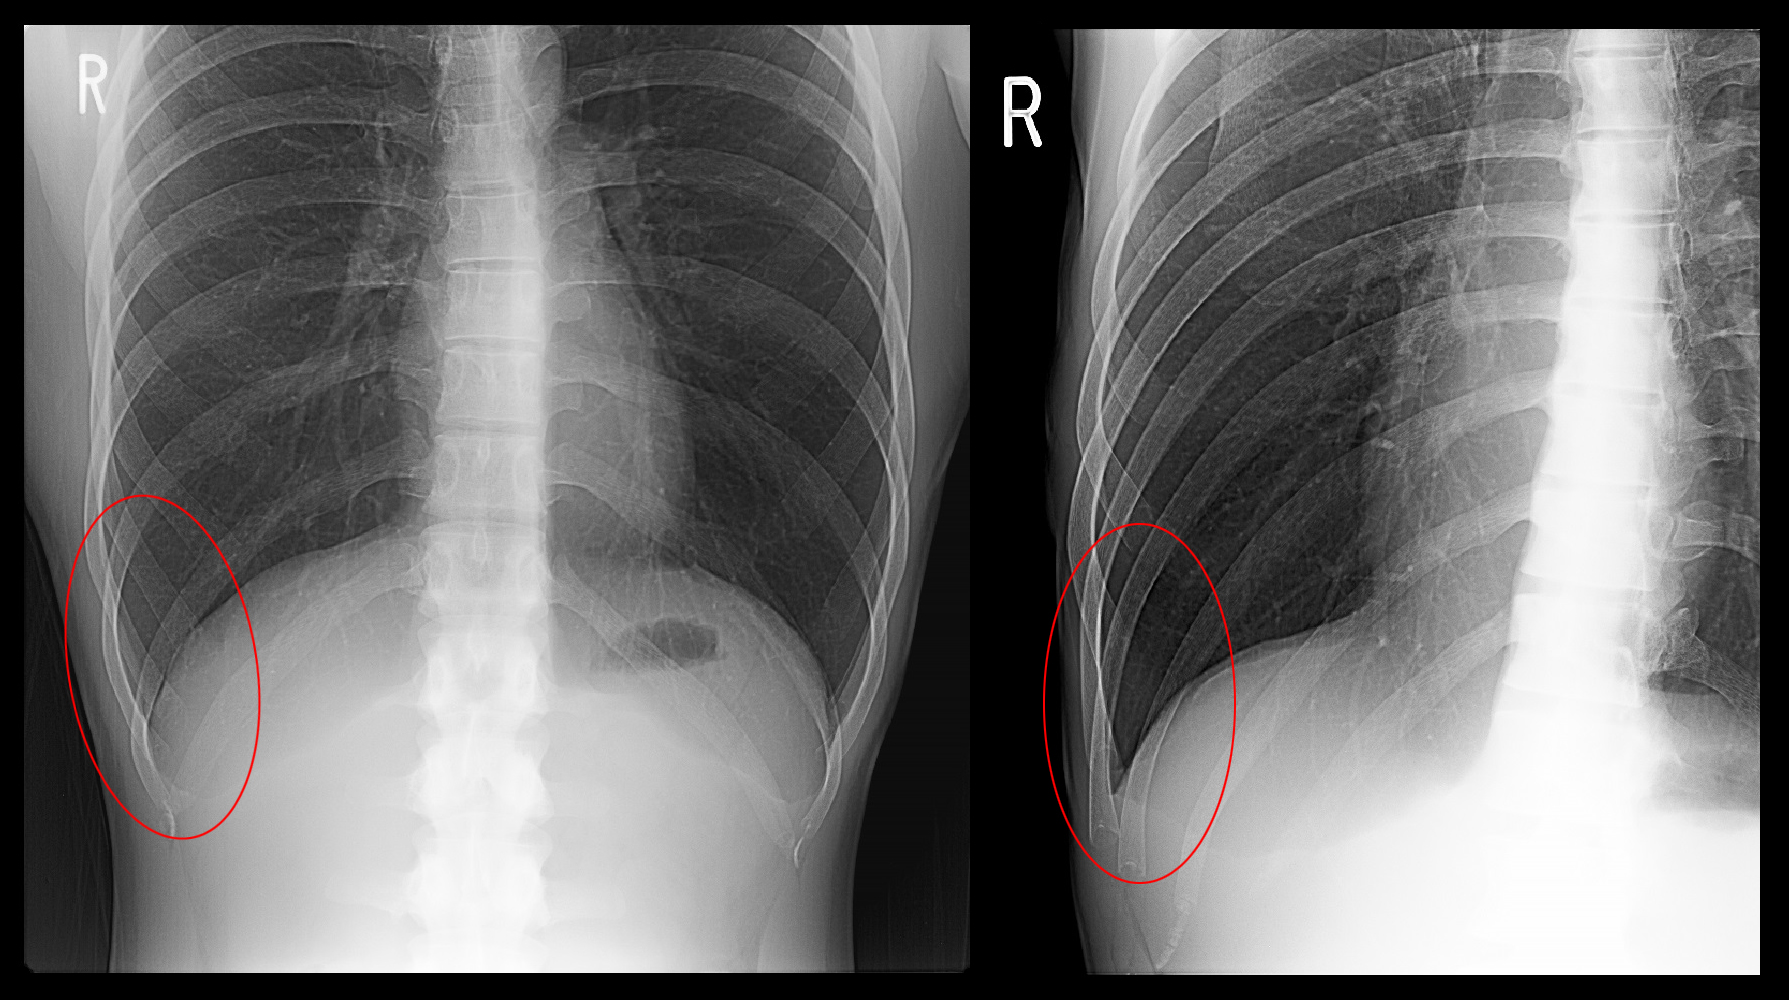

MR水平断.jpg

MRI検査では右第8・第9肋骨の前方先端部分に高輝度(健側左側と比較して白く描出される)所見が確認でき、疲労骨折と診断しました。

縦方向のMRI所見で、2か所の肋骨に高輝度所見が目立ちます。その上の肋骨も軽度の高輝度を示していますが、それは健側も同様で病的な状態とは評価しません。